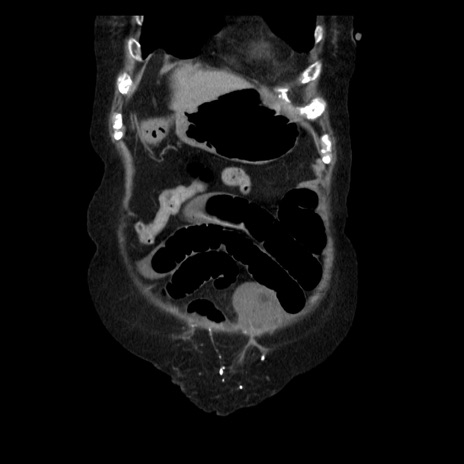

症例14(冠状断像)

【症例】 90歳代女性

【主訴】 腹痛・嘔吐

【現病歴】今朝から左側腹部痛を認めた。 経過観察していたが、嘔吐を認めたため来院。

【既往歴】 子宮癌術後

【身体所見】 意識清明、BP 127/54mmHg、P 98bpm Sp02 95%(RA)、BT 35.8°C、腹部平坦・軟腸ぜん動音聴取良好、右下腹部圧痛(+) 反跳痛なし

【データ】WBC 9800、CRP 0.46